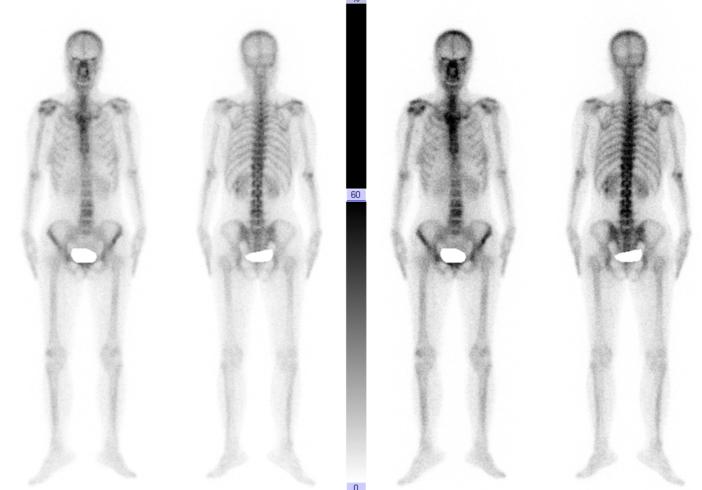

患者的Ect检查

谭磊副院长仔细阅读患者所有影像学资料后,认为患者胸11椎体侵袭性血管瘤可能性大,胸11椎体被肿瘤破坏近2/3,如果不及时治疗,不恰当的活动可能导致椎体骨折,造成严重脊髓功能障碍而致瘫痪。当机立断,经穿刺活检病理回报考虑为血管瘤,ECT检查未发现其他部位有肿瘤的存在。